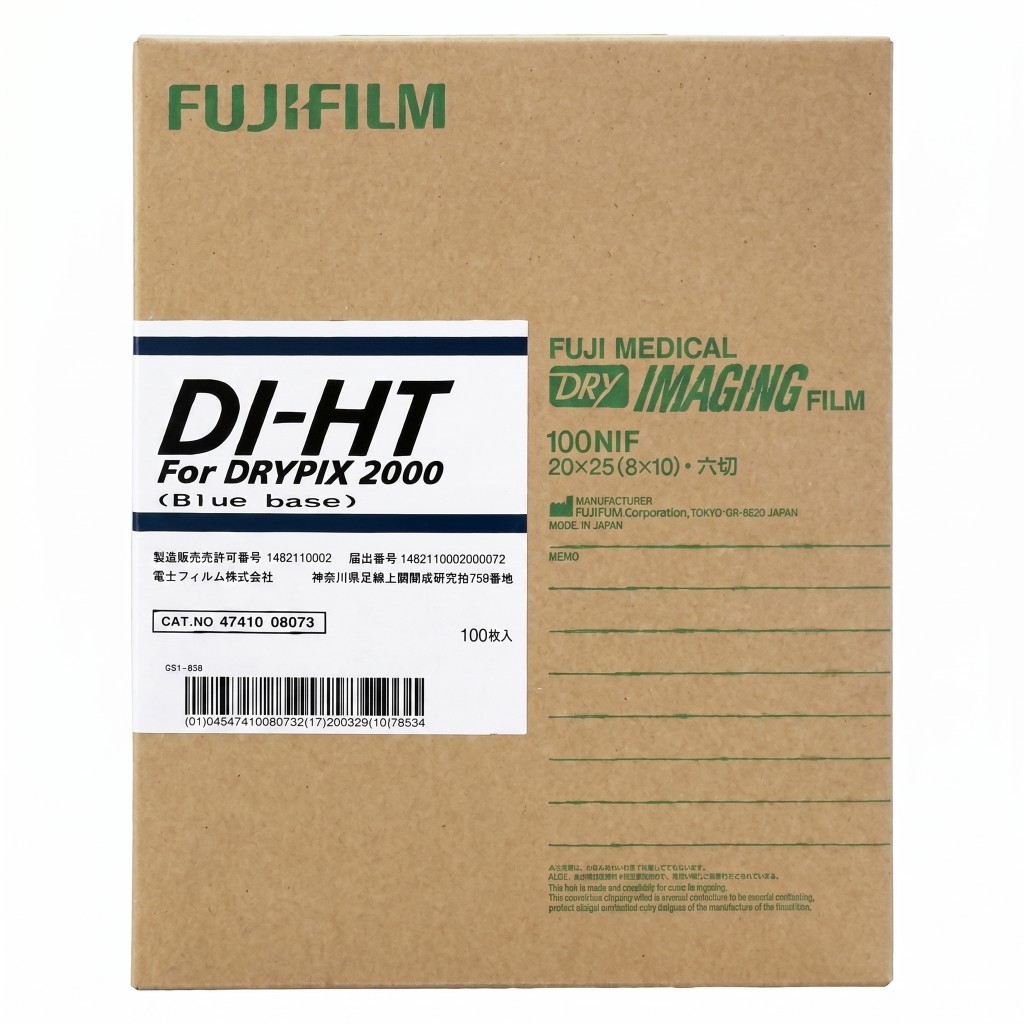

Products

We provide reliable service for our partners all around the globe. Offering well-known brands such as Fujifilm Healthcare, Carestream Health, Konica Minolta Healthcare and many others. Minimum order quantity is 1 pallet.